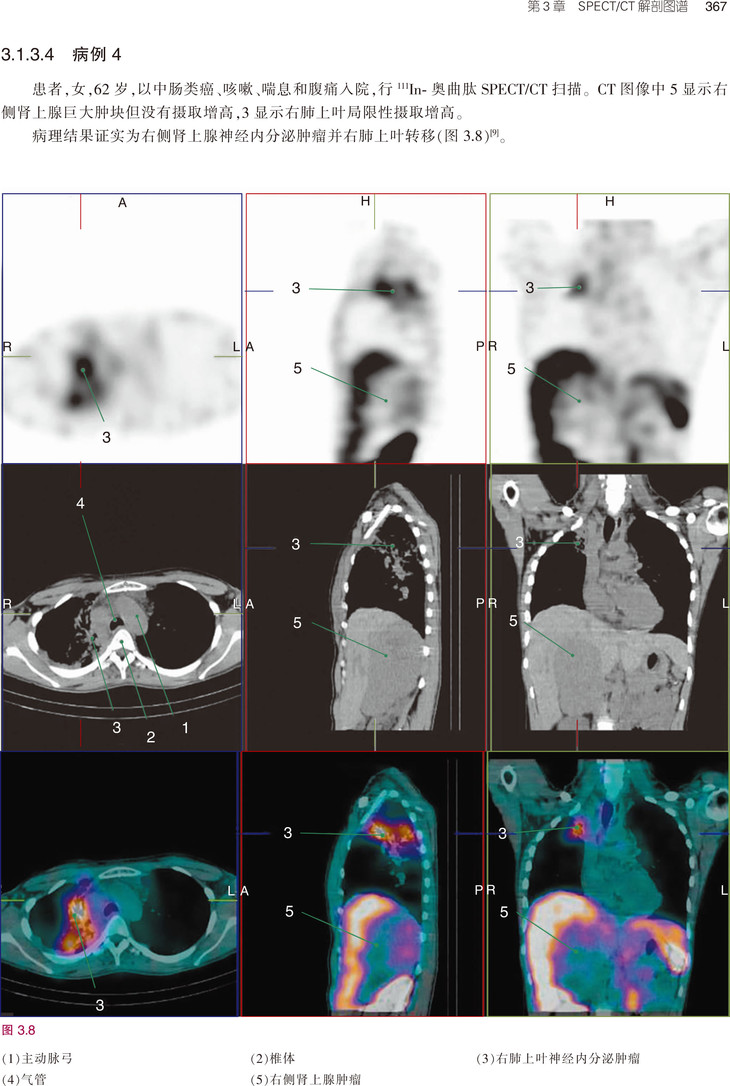

《PET/MRI, PET/CT及SPECT/CT解剖图谱》是目前融合医学影像的经典著作,书中既讲解了基础解剖内容,又有丰富的病例介绍。全书共3章内容,分别为PET/MRI解剖图谱、PET/CT解剖图谱和SPECT/CT解剖图谱。第1章PET/MRI解剖图谱按照大脑、头颈部、胸部、腹部、盆腔、肌肉骨骼系统进行描述。第2章PET/CT解剖图谱按照FDG和非-FDG进行分类描述。第3章则描述了肿瘤、骨和其他病变的SPECT/CT表现。本书编者临床经验丰富、理论基础扎实、科研能力出众,以“融合图像”作为突出特色,荟萃了当今最为先进的PET/CT、PET/MRI及SPECT/CT技术,有助于提升国内从业人员的专业素养、优化诊断思路,进而更好地服务于患者。